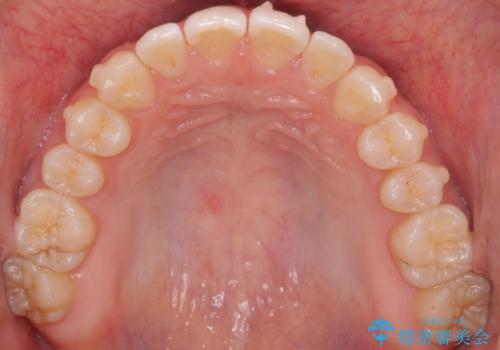

咬んでも向こう側が見える、前歯が閉じない症状でした。また、上の前歯が少し前に出ている状態でした。

上の前歯をわずかに削る処置を行い、後ろに下げながら下の歯となるべく咬むように矯正治療を行いました。